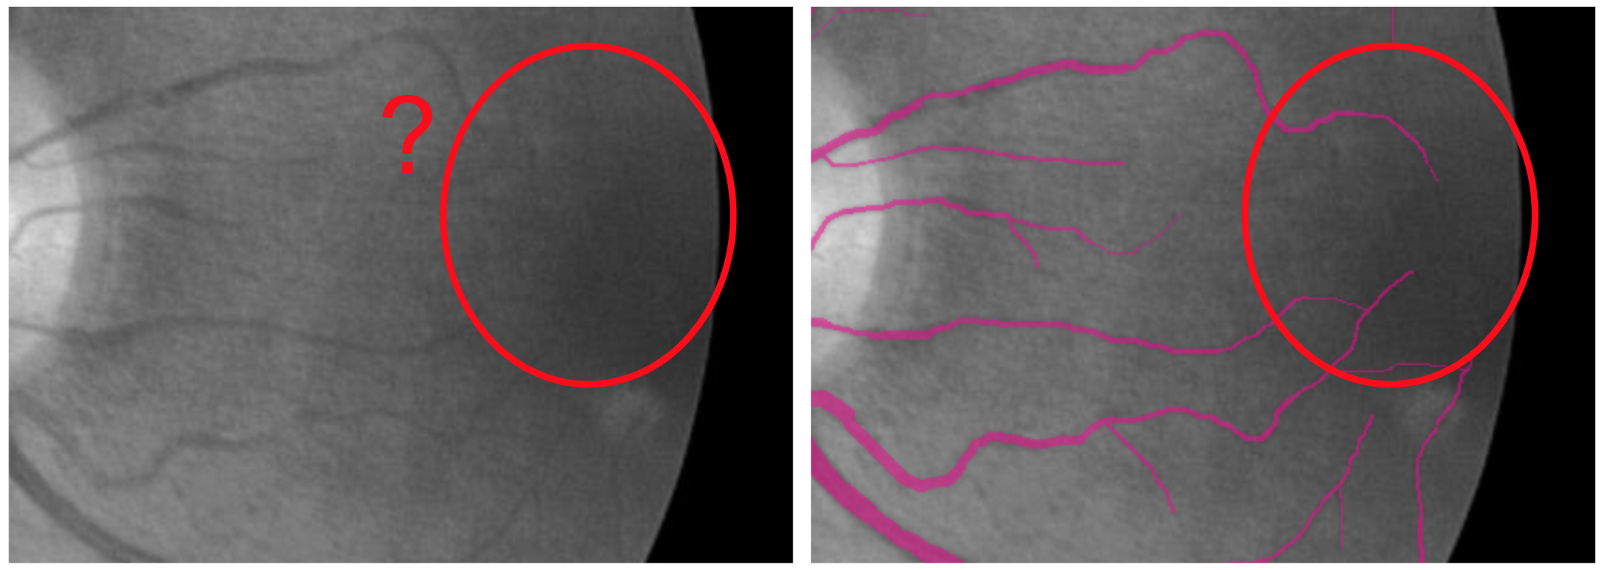

Hello world! In December of 1895, Wilhelm Röntgen the bones of his wife’s hand in the first X-ray photograph. “I have seen my death,” she said. This breakthrough had an incredible influence on 20th-century medical treatment. And latest Deep Learning advances open up new possibilities in this field. revealed Deep Learning has found great success in computer vision and other areas. And now it is actively transforming the world of medicine. AI helps doctors make more accurate diagnoses faster. Today we would like to share our thoughts and investigations into very promising direction: Human in the loop AI for medical image analysis within a single environment — . Supervisely Our platform allows to manage and annotate data, train NNs, apply them for automatic pre-annotation and then deploy them as API. Challenges with medical images IBM researchers that medical images, as the largest and fastest-growing data source in the healthcare industry, account for at least 90 percent of all medical data. estimate Challenge 1: data privacy Medical data is still personal and not easy to access. And due to data privacy concerns most of the public health centers are reluctant to share the data. Challenge 2: size of annotated data Annotation process is hard to outsource and only expert physicians can analyze medical images. This limitation leads to high costs and to the lack of annotated data. Challenge 3: quality of annotation tools Annotation tools, that can be used to extract insights from medical images, are still limited, in most cases publicly unavailable and requiring most analysis to be done manually. Challenge 4 (consequence of 1 and 2): segmentation challenge Datasets for segmentation task are typically extremely small compared to large public datasets of common images (COCO, PascalVoc and so on). Due to the size of datasets it is difficult to train very deep neural network architectures. Objects of interest can vary in size, shape and position. In combination with the “soft” boundaries it produces additional problems. Our goals We are going to overcome Challenge 3 and Challenge 4: give the industry end-to-end solution that makes human experts more efficient and automates routine tasks with powerful AI technologies. Supervisely: user interfaces We realize, that there is still a lot of work ahead: increase the number of convenient annotation tools and add the support of DICOM format, three dimensional images, sequences of images and so on. But these are only technical issues, first steps are already done and promising results are obtained. We are passioned to accelerate medicine and happy to be a part of global research community that drives deep learning revolution to healthcare. There could be no more important application of this new capability [deep learning] than improving patient care — Jensen Huang, NVIDIA CEO and co-founder Case-study: blood vessel segmentation in retina images There are a lot of Deep Learning medical applications in imaging: tumor detection, tracking tumor development, blood flow quantification and visualization, dental radiology and much more. Because we are not doctors, we looked for data we understand more or less. That’s why we decided to make research on blood vessel segmentation. Let’s take a look to one of the most popular public datasets in this field: (STructured Analysis of the Retina). STARE Dataset contains 28 annotated images with resolution 999 × 960. We consider the case that we have only . Other images will be used for final evaluation of quality. All training images are below: 6 annotated images in training dataset Here is the whole training dataset we use. This scenario is pretty close to real world: medical doctor annotates few images, then neural network is trained on this data and applied to other images for pre-segmentation. Then doctor just corrects the NN predictions. Such approach is called Human in the loop AI. It is aimed to significantly accelerate efficiency of human expert. PS. Thanks to Supervisely entire research took 2 hours without haste ☕. Step1: training data augmentation We had only 6 annotated images. To train NN we have to automatically increase the size of dataset. Supervisely has special module to perform augmentations: DTL (Data Transformation Language). It allows to configure entire augmentation process in a simple json-based format and perform it in a few clicks. How DTL query interface looks like In this use case we did horizontal/vertical flips and relatively big random crops. We got 264 training examples from only 6 annotated images. Here is the visualization of computational graph that we applied to our data: Resulted crops after augmentation Step2: train neural network There are few state of the art Neural Networks for semantic segmentation in Supervisely. One of them — our custom UNet-like architecture. It was chosen because: we have small training dataset, it is accurate and fast to train. Also we use combination of Binary Cross Entropy and Dice losses because of class imbalance problem. Vessels pixels covers only few percents of image area in contrast to background pixels. We trained NN 50 epochs. It is interesting to visualize Neural Network predictions during training. We take unseen image and apply NN after each epoch. Here you can see how our NN becomes smarter over time. Supervisely supports multi GPU training. Each epoch takes around 20 seconds on four GPU. Total training time — around 17 minutes. Step3: automatic pre-segmentation We applied NN to new images. Let’s compare predictions with ground truth. : NN predictions, : ground truth Left Right As you can see from this comparison every relatively bold vessels are segmented. There is no noise. It means that the human only have to draw few hairlines with “polyline” tool. Also, as we understand real data has much bigger resolution that public data we use in this experiment. We think that this fact is crucial for the quality of hairlines segmentation. Resolution of publicly available images is not enough. Look at this example: do you see the vessels that are annotated by doctors? Left: meme, Middle: original image, Right: doctor’s annotation Step4: manual correction As you can see from images above the quality of automatic pre-annotation is pretty good. It is much more easier and faster to correct NN predictions than annotate from scratch manually. We were not lazy and made time measurements: how much time we need for manual annotation from scratch vs correction of NN predictions. Manual annotation from scratch: . Correction of NN predictions: . 36 minutes / image 4 minutes / image Conclusion is obvious. Final thoughts Deep Learning has a huge potential in medical image analysis. AI is changing the way doctors diagnose illnesses. Main important difference between doctor and deep learning algorithm is that doctor has to sleep. Neural Network can process millions of images and can be continuously improved. Human in the loop approach and automatic segmentation with Supervisely will let us create large datasets faster. All steps are done without coding. It means that user with no ML background have access to state of the art AI. So ML community will build more services to help doctors provide better and quicker treatment. Let’s make the future together. If you found this article interesting, then let’s help others too. More people will see it if you give it some 👏.